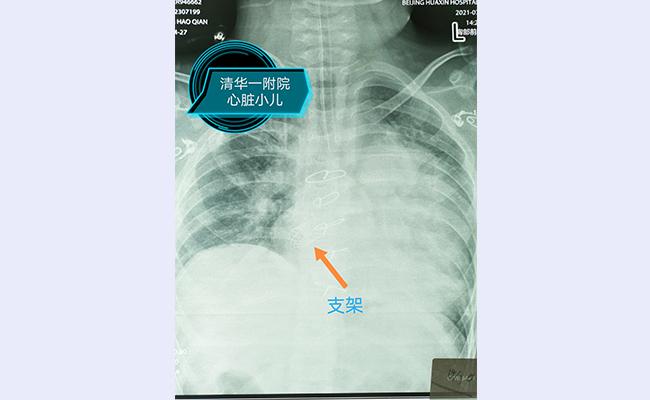

手术选择在杂交手术室进行,在几乎没有明显出血的情况下,靳永强顺利游离肺组织,显露左侧心房。在食道超声的引导下准确选择心房穿刺部位,使穿刺部位在板障狭窄的正下方,顺利将球囊支架系统通过狭窄部位;采用食道超声及X线下确定支架植入部位,操作如行云流水般一次性扩张成功,食道超声及导管测量板障处血流畅通,无明显压差。患儿术后恢复顺利,3小时后撤除呼吸机,第二天便转回普通病房。回到病房的小千活动量明显好转,睡觉时终于可以平卧了。术后超声提示肺动脉压力明显降低,左心室的射血分数也恢复至正常,甚至主动脉瓣的反流也从中量降至少量。

顺利植入支架